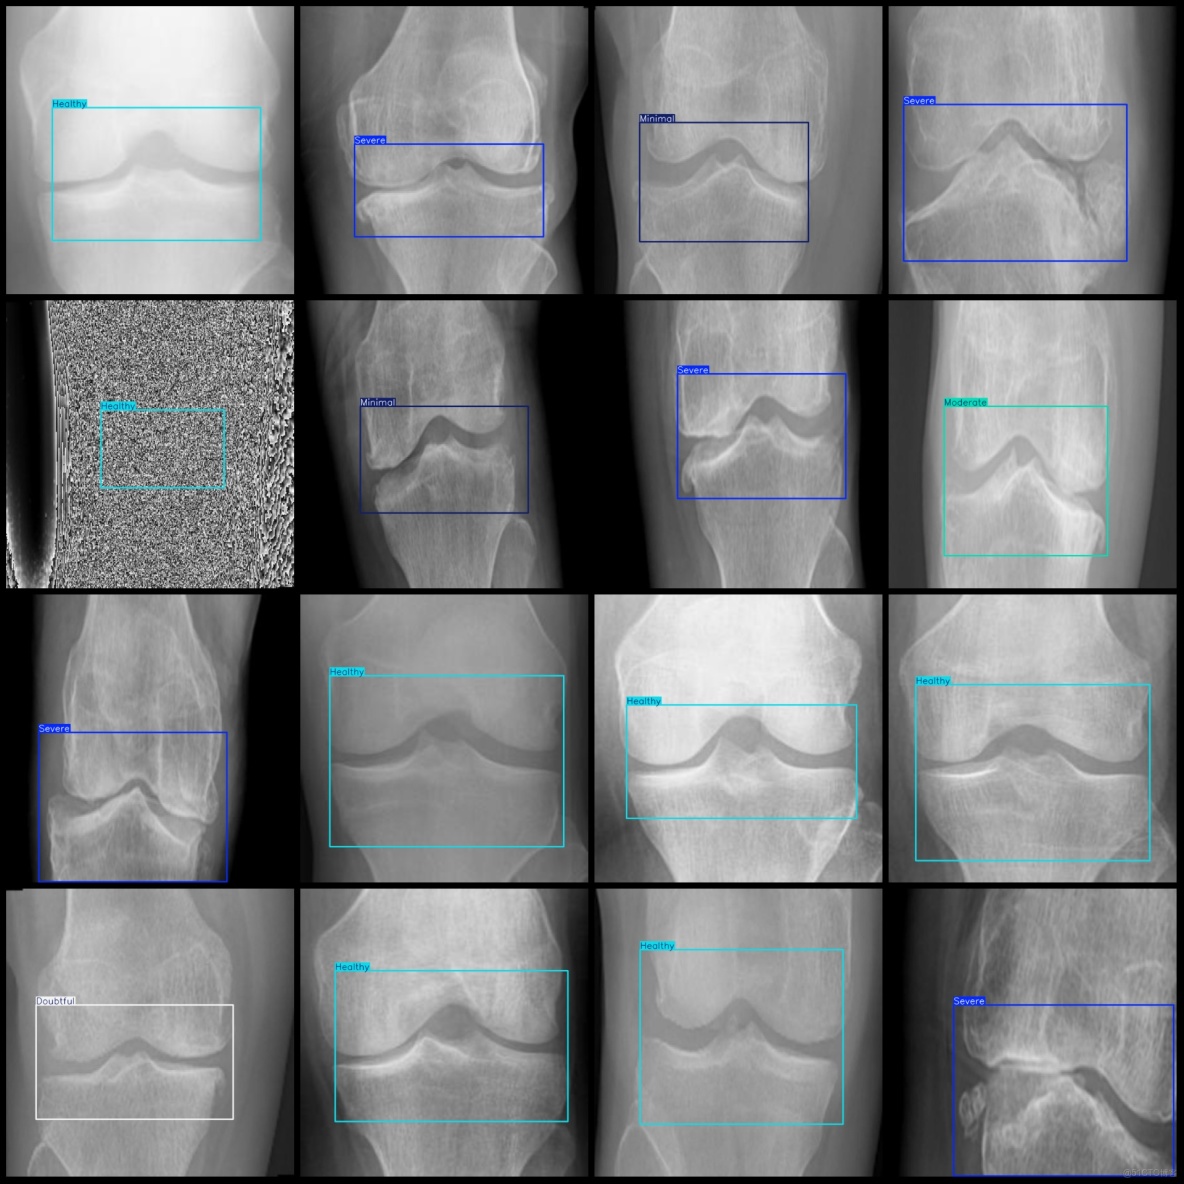

標註例子:

智慧醫療膝蓋骨關節炎嚴重程度檢測數據集VOC+YOLO格式8000張5類別_txt文件_03

智慧醫療膝蓋骨關節炎嚴重程度檢測數據集VOC+YOLO格式8000張5類別_xml文件_04

標註類別名稱(注意yolo格式類別順序不和這個對應,而以labels文件夾classes.txt為準):["Doubtful","Healthy","Minimal","Moderate","Severe"]

每個類別標註的框數:

Doubtful (待定) 框數 = 1414

Healthy (健康) 框數 = 3700

Minimal (極輕度) 框數 = 819

Moderate (中度) 框數 = 730

Severe (重度) 框數 = 1337